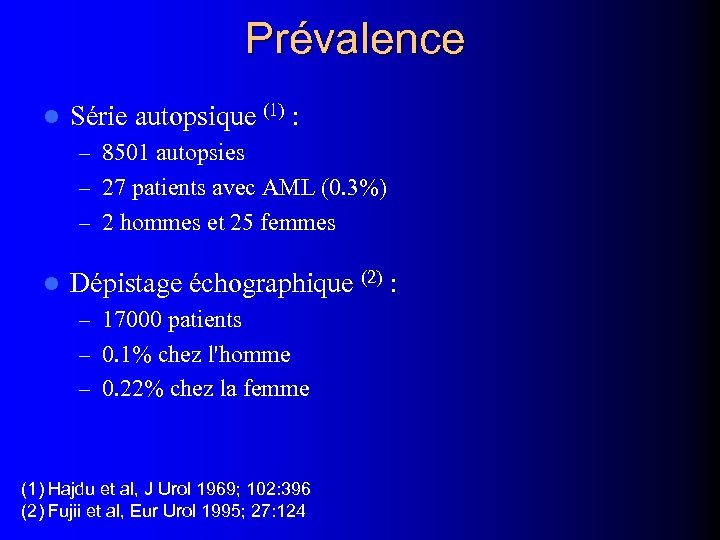

Prévalence l Série autopsique (1) : – 8501 autopsies – 27 patients avec AML (0. 3%) – 2 hommes et 25 femmes l Dépistage échographique (2) : – 17000 patients – 0. 1% chez l'homme – 0. 22% chez la femme (1) Hajdu et al, J Urol 1969; 102: 396 (2) Fujii et al, Eur Urol 1995; 27: 124

Prévalence l Série autopsique (1) : – 8501 autopsies – 27 patients avec AML (0. 3%) – 2 hommes et 25 femmes l Dépistage échographique (2) : – 17000 patients – 0. 1% chez l'homme – 0. 22% chez la femme (1) Hajdu et al, J Urol 1969; 102: 396 (2) Fujii et al, Eur Urol 1995; 27: 124